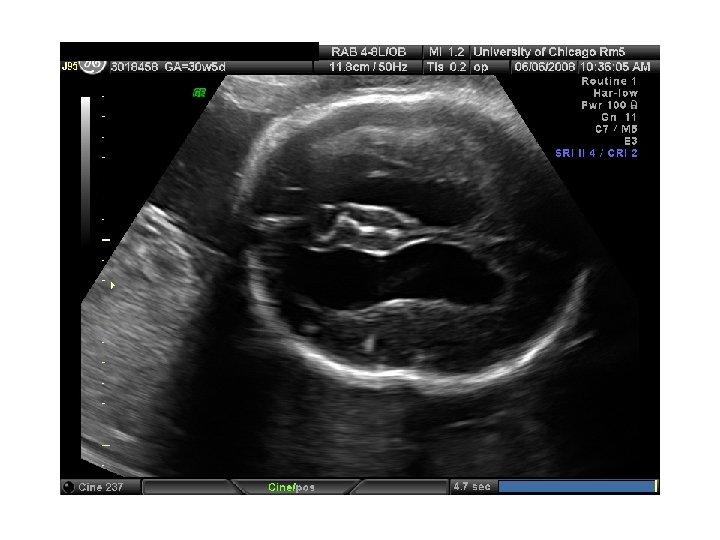

QUIZ What is Your Diagnosis? Case: Patient J. F. 30 years old, at 32 week gestation. Presented with the following pictures.

Answer: a) Trisomy 21 b) Non-immune Hydops c) Paravo virus Infection